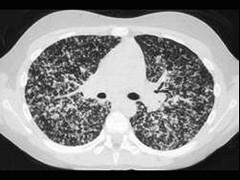

肺结核的好发部位是 ( )A、右肺上叶B、右肺下叶C、左肺上叶D、左肺下叶E、肺尖

问题 肺结核的好发部位是 ( )

选项 A、右肺上叶 B、右肺下叶 C、左肺上叶 D、左肺下叶 E、肺尖

答案 E